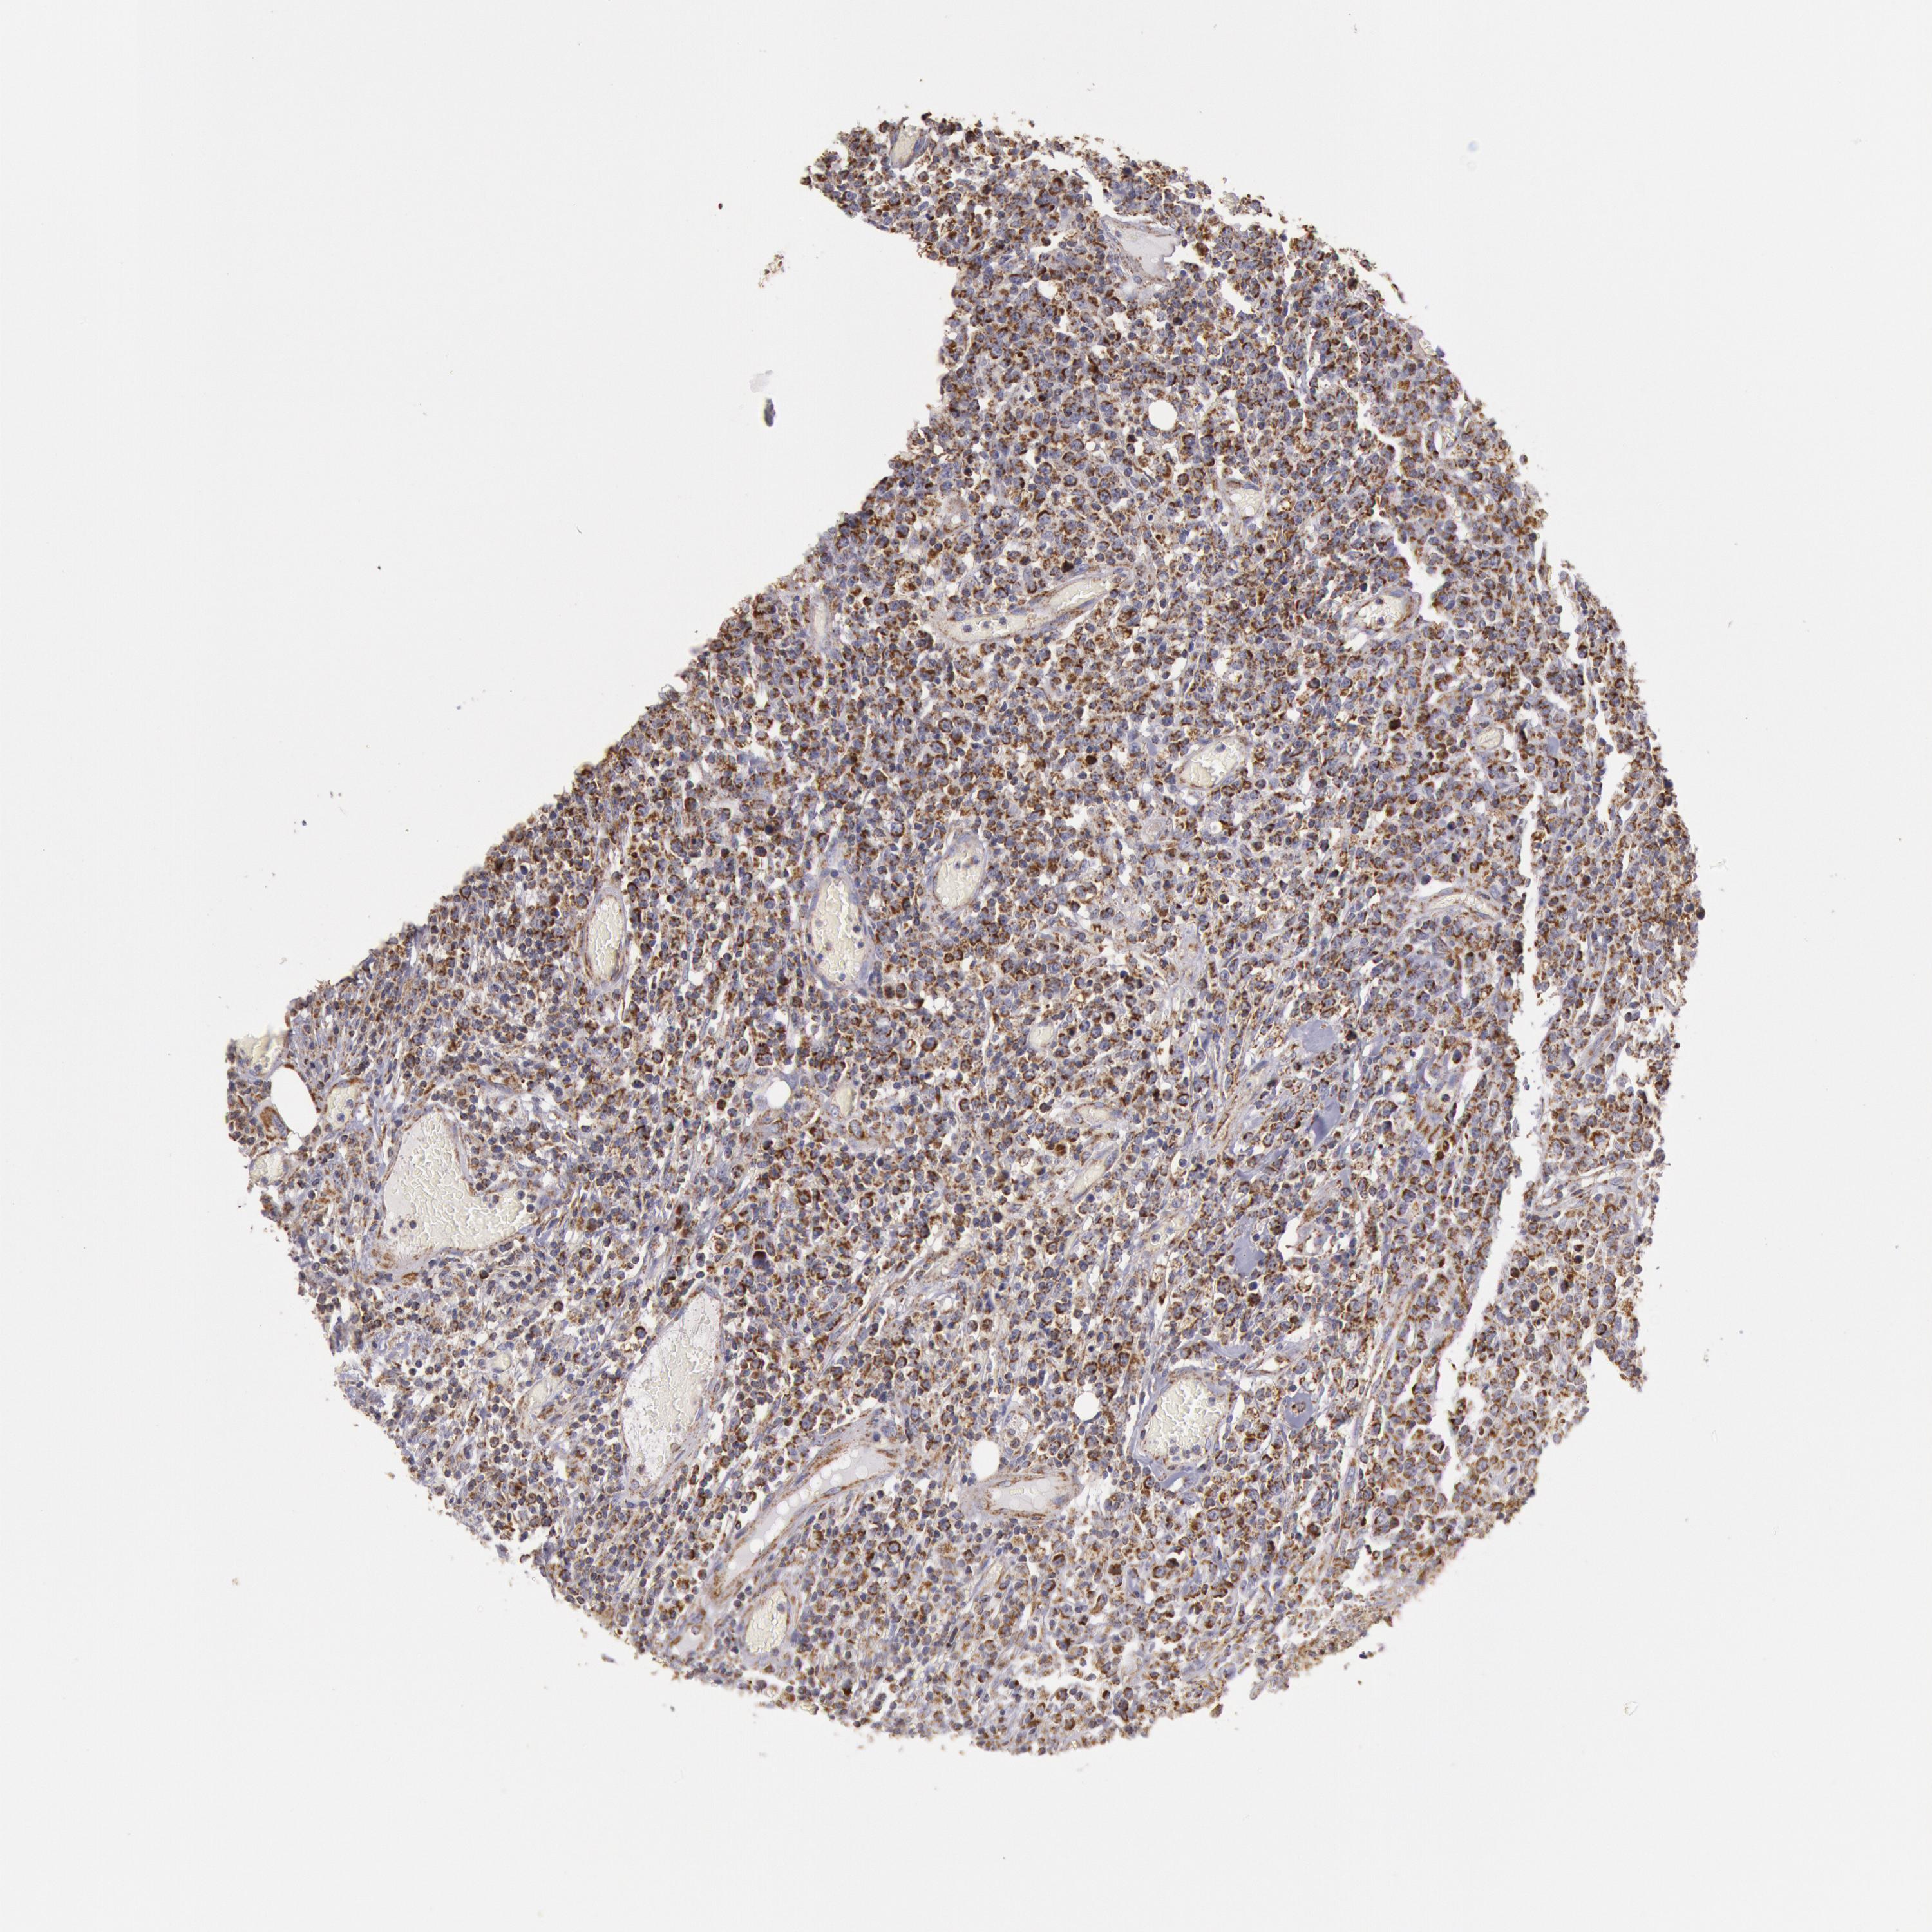

LYMPHOMA - Protein expressioni

A mouse-over function shows sample information and annotation data. Click on an image to view it in a full screen mode. Samples can be filtered based on level of antibody staining by selecting one or several of the following categories: high, medium, low and not detected. The assay and annotation is described here.

Antibody stainingi

Antibody staining in the annotated cell types in the current human tissue is reported as not detected, low, medium, or high, based on conventional immunohistochemistry profiling in selected tissues. This score is based on the combination of the staining intensity and fraction of stained cells.

Each image is clickable and will lead to virtual microscopy that enables deeper exploration of all samples and also displays staining intensity scores, fraction scores and subcellular localization as well as patient and tissue information for each sample.

Antibody HPA001247

Staining

High

Intensity

Strong

Quantity

>75%

Location

Nuclear

Malignant lymphoma, non-Hodgkin's type, High grade